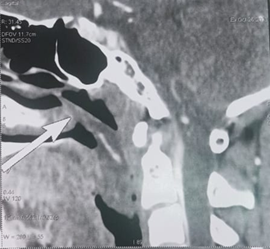

computed tomography (CT) scan of the of face revealed a mass of cystic density

filling the lumen of the nasopharynx and the upper part of the oropharynx which

was non-enhanced after contrast injection. However, all the paranasal sinuses

were clear (Figure 2). MRI of the

Figure 2. Axial and sagittal sections of a CT scan of the face: shows a mass of cystic density which is inserted into the middle turbinate and extends into the nasopharynx (a,b) and oropharynx (a,b,c).